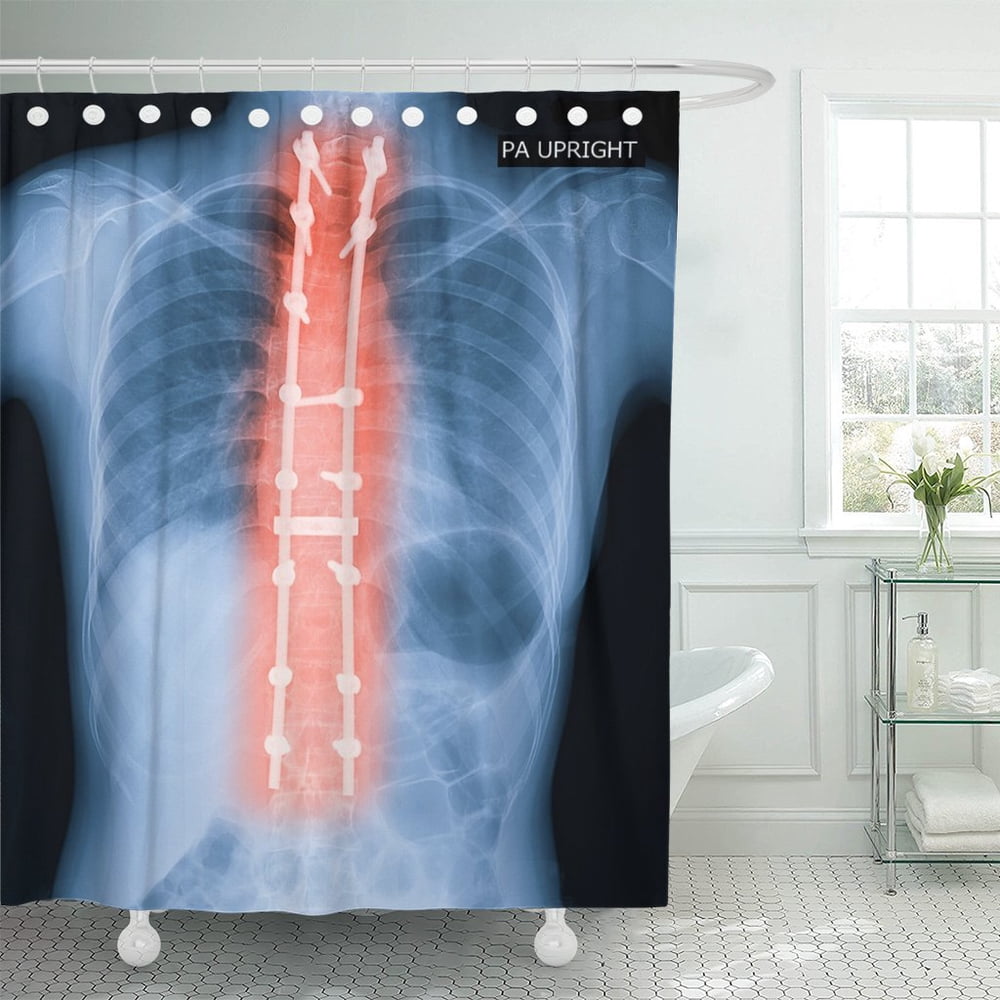

From www.walmart.com

PKNMT X Ray of Adult Patient Spine Show Scoliosis Surgery Shower When Can You Shower After Scoliosis Surgery After your surgery you will be brought to a recovery room and woken up, you will be monitored and given pain medication. You might stay the night before or arrive on the morning of your surgery. Cover the bandage with lots of waterproof tegaderms and such. When can i shower after my surgery? You can take a shower three days. When Can You Shower After Scoliosis Surgery.